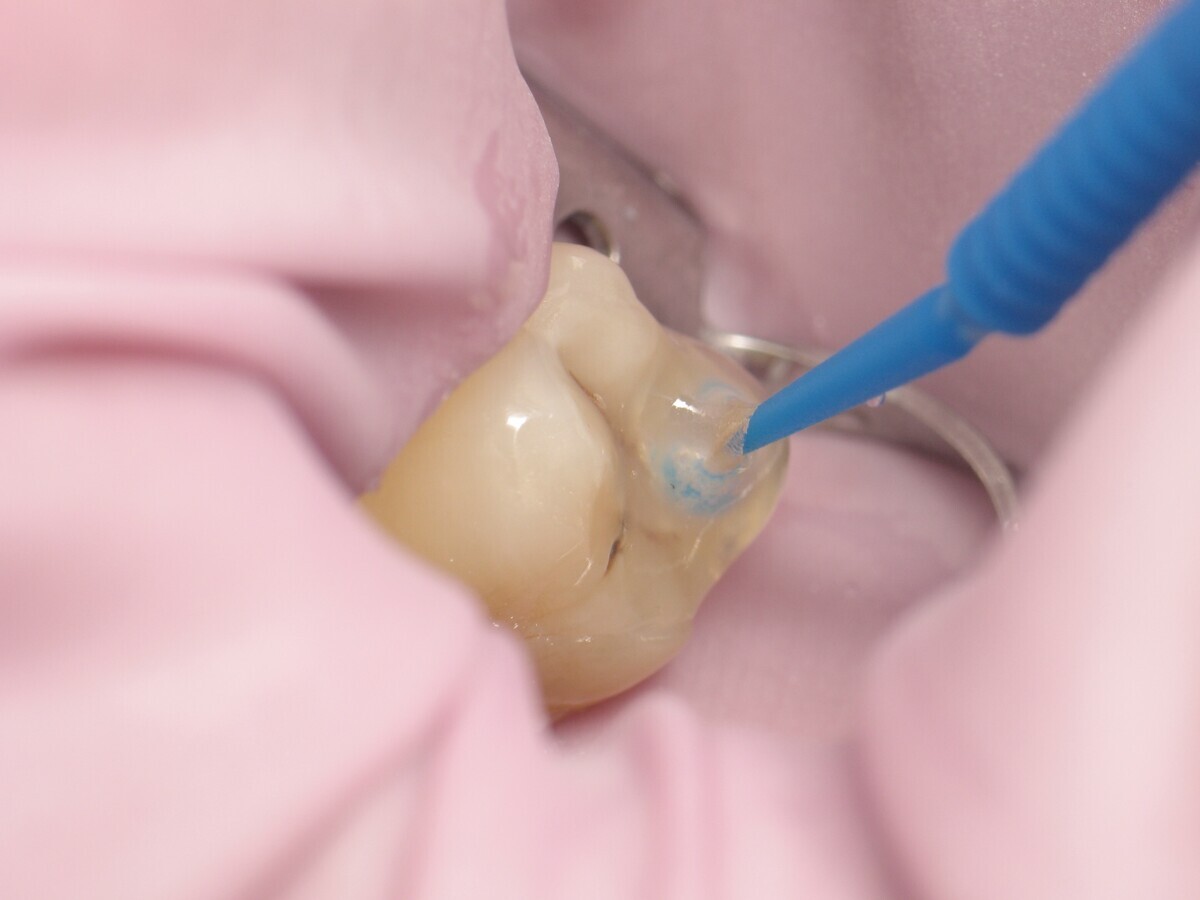

Este artículo describe el tratamiento de una cavidad clase I en un molar utilizando un composite termoviscoso mediante la técnica de la almohadilla (Figura 1). En primer lugar, se registran los detalles anatómicos utilizando una resina transparente, fluida y fotopolimerizable (Clip Flow, VOCO). El diente se aísla con un dique antes de aplicar el composite transparente a la superficie oclusal con un cepillo aplicador y fotopolimerizar durante 10 segundos (Figuras 2-4). La almohadilla oclusal así obtenida (Figura 5) debe almacenarse en alcohol (etanol o isopropanol) para eliminar la capa de inhibición. Luego se limpia la cavidad clase I (Figuras 6 y 7). A continuación se graba el esmalte durante 30 segundos y la dentina durante 15 segundos (Conditioner 36, Dentsply Sirona) y luego se enjuaga bien (Figuras 8 a 10). Debido al bajo espesor de la dentina remanente, también se aplica protección pulpar (Telio Desensitizer, Ivoclar Vivadent) (Figura 11). Luego se frota el adhesivo sobre las superficies dentales durante 20 segundos (Futurabond DC, VOCO), luego se seca bajo una pulverización de aire sin aceite graso durante 5 segundos y luego se fotopolimeriza durante 10 segundos (Figuras 12, 13). Para una humectación óptima, el fondo de la cavidad se cubre con un compuesto fluido de baja viscosidad (GrandioSO Light Flow, A3.5, VOCO) y se fotopolimeriza durante 20 segundos (Figuras 14, 15). Utilizando el Dispensador VisCalor, un dispensador portátil que permite el calentamiento y la aplicación simultánea de resinas, la cavidad se llena luego con un composite termoviscoso bulk (VisCalor Bulk, A2, VOCO).

Figura 03. Aplicación de Clip Flow con un pincel aplicador.

Figura 04. Fotopolimerización de Clip Flow.